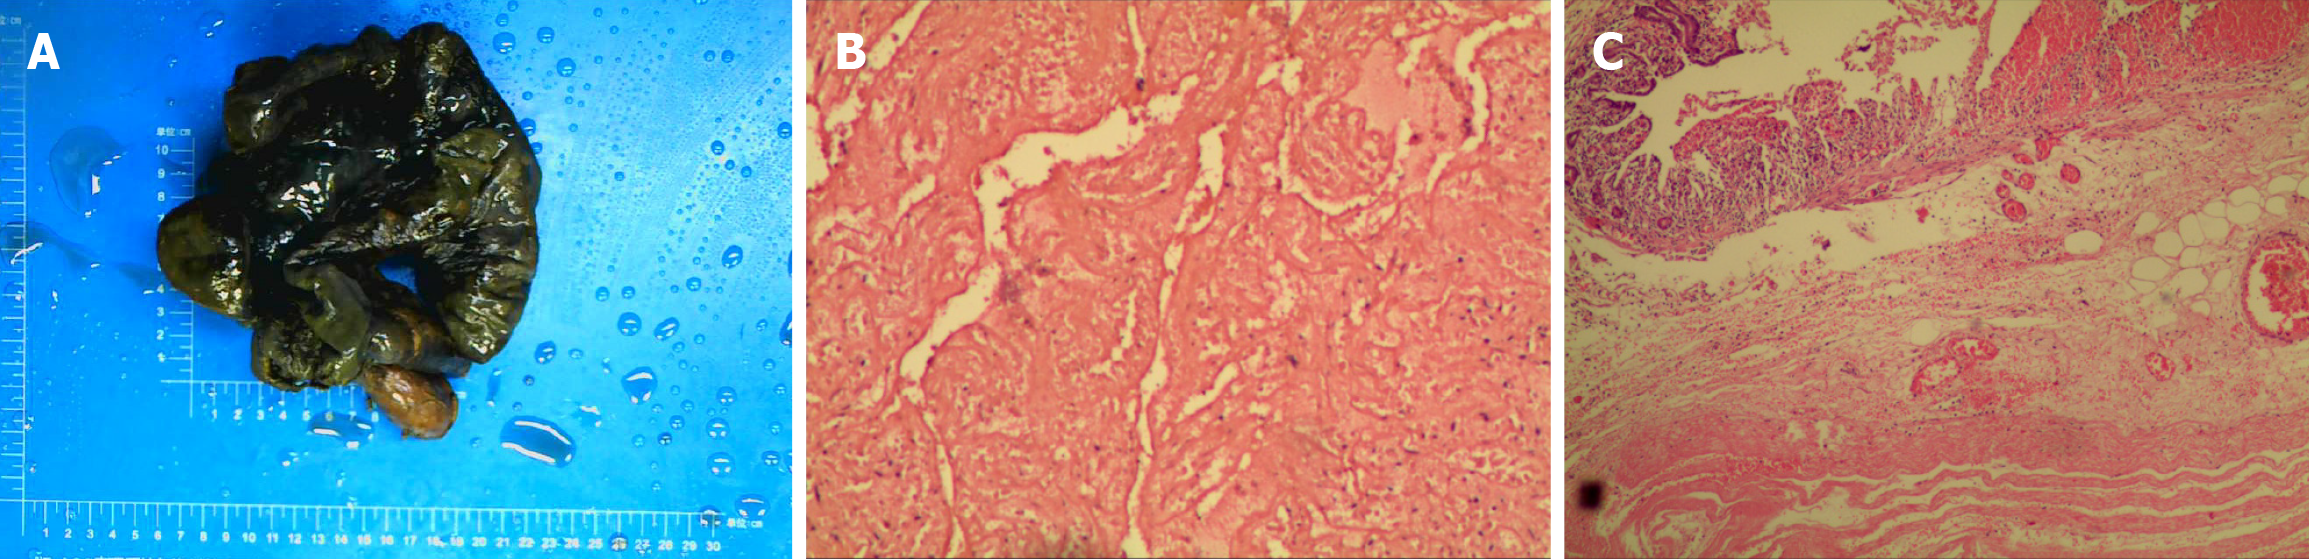

Figure 1 Intestinal infarction specimens and microscopic findings.

A: Necrotic bowel; B: Only the tissue structure can be seen in the muscular layer [hematoxylin & eosin (H&E) 100 ×]; C: The mucosa adjacent to the necrotic bowel exhibited lymphocytic and plasmacytic infiltration, with focal chronic enteritis and approximately 10 eosinophils per high-power field (H&E 20 ×).